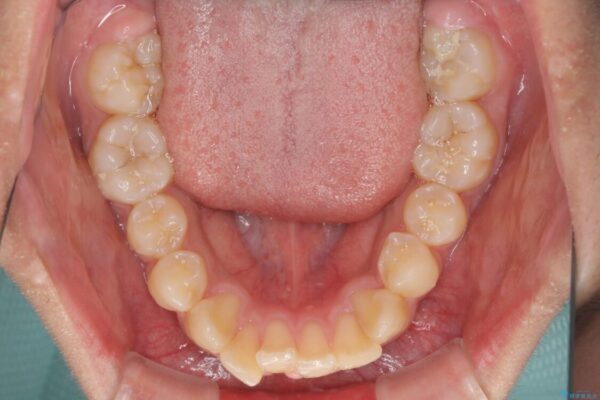

治療前

• 膨らんだ口元 ワイヤー装置での抜歯矯正 治療前画像